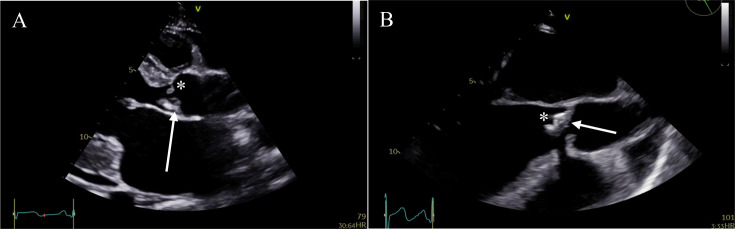

Methods and results: Data from the Tygerberg Endocarditis Cohort Study were evaluated between October 2019 and May 2023. Continuous variables were reported as mean with SD if normally distributed, alternatively as median with IQR. Categorical variables were reported as counts and percentages. A Kaplan-Meier curve will be used to depict the mortality rate of operated versus unoperated patients. The mean age (±SD) was 38±9 years, 70.9% were male, 25.8% were either homeless or lived in informal housing, 70.9% were unemployed, 54.8% had an underlying alcohol-use disorder and 25.8% were HIV positive. Blood serology was positive (IgG titre ≥1:256) in 96.7% of patients with available sera. Valvular tissue was available for PCR testing in 18 cases. Of these, Bartonella quintana was identified in 16 cases and Bartonella henselae in one case. None of the cases with both serology and valve PCR data had negative serology. No cases of blood culture-positive endocarditis (BCPE) had a positive PCR for Bartonella spp. The most common isolated valve lesion on echocardiography was severe aortic regurgitation (43.3%). The 1-month and 6-month mortality in the operated cohort was 0% and 4.5%, respectively.

Discussion: Bartonella quintana is the most common cause of BCNE accounting for 49.2% of cases at our centre. None of the PCR-proven cases of Bartonella endocarditis had negative serology, which suggests that the test has a high negative predictive value. The current guideline diagnostic titre of ≥1:800 is assay dependent and is not generalisable to alternative, commercially available, assays. Crucially, none of the BCPE cases with available PCR on valve tissue had a positive PCR for Bartonella spp, suggesting a positive valve PCR is definitive evidence of true infection in an endemic region. The specific clinical, echocardiographic and mortality data were consistent with the reported literature and characterised a subacute, but ultimately destructive endocarditis with a high embolic risk and underscores the need for early surgical intervention.